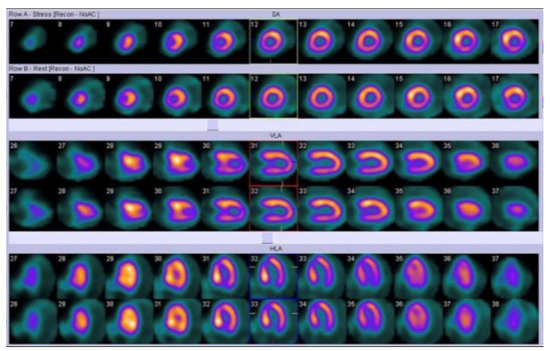

5.2. Nuclear Imaging Application in Pediatric Cardiomyopathies

5. Role of Nuclear Medicine Imaging in Pediatric Cardiomyopathies

5.1. Protocols